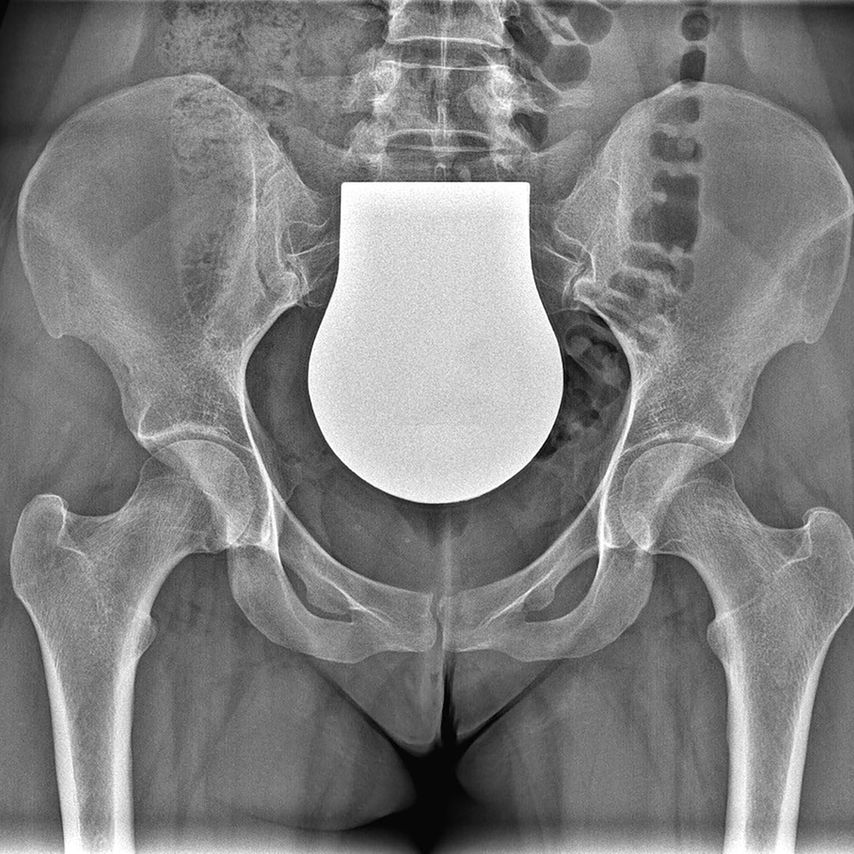

Intraoperative Bildgebung als Fehlerquelle hinsichtlich der Pfannenversion

Die intraoperative Reorientierungs-Position des Pfannenfragmentes auf Basis von Durchleuchtungsbildern in liegender Position stellt derzeit immer noch eine große Herausforderung für jeden Chirurgen dar. Die Ursachen dafür liegen einerseits in der posterior-anterioren Röntgenstrahlrichtung und der geringen Film-Fokus-Distanz der intraoperativen Durchleuchtung im Vergleich zur konventionellen Beckenröntgenaufnahme, andererseits in einer veränderten Beckenkippung im Liegen im Vergleich zur stehenden Position. Diese Faktoren verändern die Darstellung der Pfannenversion intraoperativ. Da aber sowohl eine Unter- als auch eine Überkorrektur der Pfannenversion zu klinisch schlechteren Ergebnissen und in der Folge zu einer erhöhten Arthroserate führt, ist auf die Pfannenversion besonders zu achten.5 Die Verwendung von Schnitt- und Korrekturblöcken könnte hier zukünftig Abhilfe schaffen.